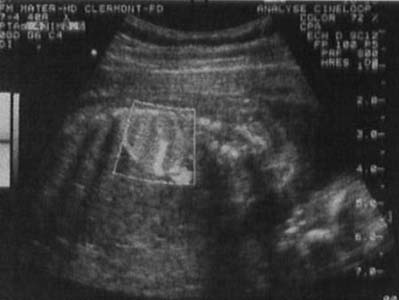

Masse hyperéchogène dans le base pulmonaire